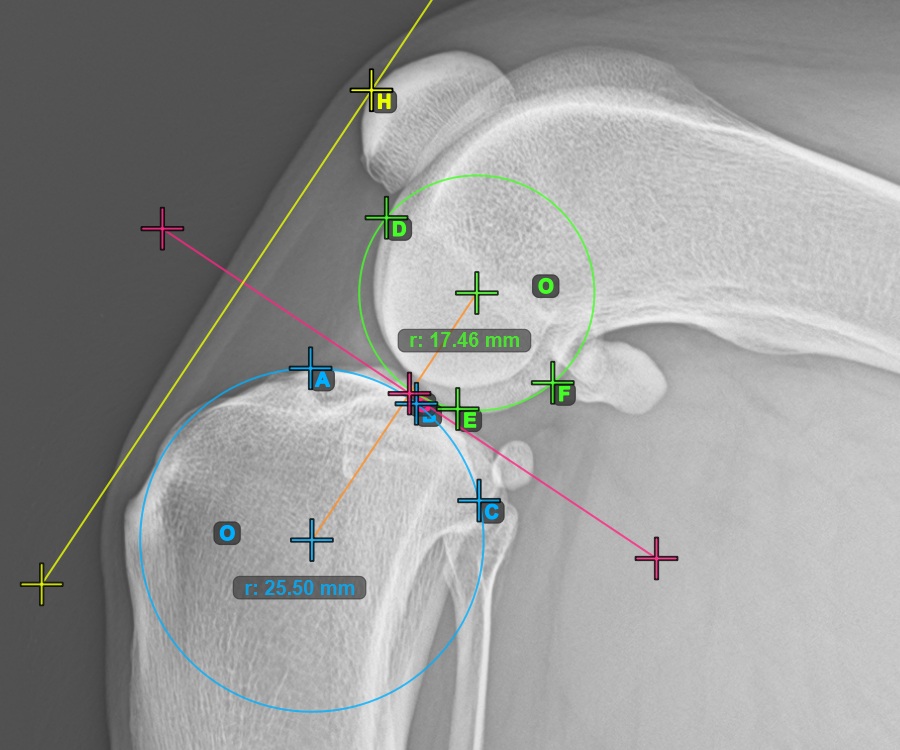

The image below represents a typical placement of the three points on the Condylus Femoris.

![]()

Mark the three points on the main condylus of the femoral bone (Condylus Femoris). Regardless of the order, make sure to mark the most cranial point, the most caudal point and the midpoint of the Condylus Femoris. A circle will be automatically constructed based on the three placed points.